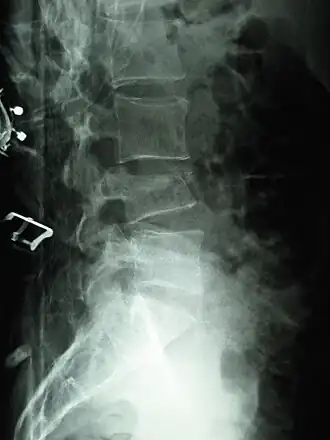

Tassement de la quatrième lombaire à la suite d'une chute.

Un tassement vertébral est une fracture correspondant à une diminution de la hauteur d'une vertèbre. Elle peut être due à un traumatisme ou à une fragilisation.

• Lorsque le mur antérieur de la vertèbre se fracture, on parle de tassement « cunéiforme » c'est-à-dire en forme de « coin », du latin cuneus.

• Lorsque l'atteinte vertébrale est globale, on parle de « vertèbre en galette ».